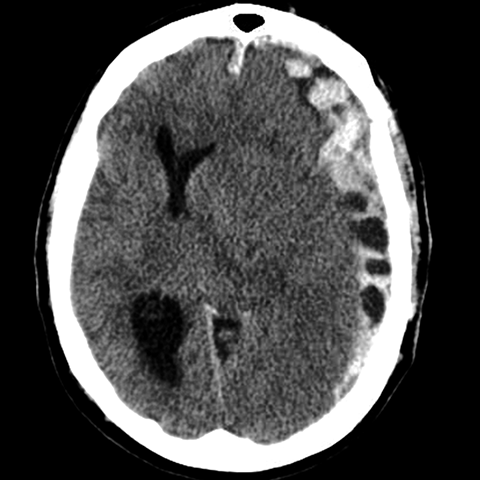

55 year old female presents to the emergency room after a car accident [2 of 4]